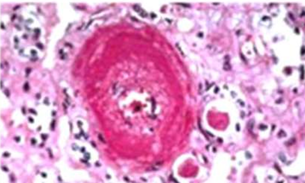

Arteriosclerosis

Hypertensive vascular disease: Malignant Hypertension

Hyperplastic ("onion-skinning") obliteration arteriolosclerosis causing luminal

Necrotizing arteriolosclerosis

Fibrinoid necrosis showing fragmented collagen & inflammation